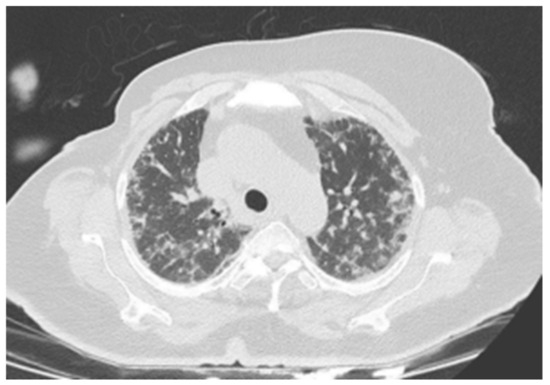

| Patient 1 | Hypersensitivity | Ribociclib | Upper lobe- |

| Pneumonitis (HP) | predominant mosaic attenuation, air | ||

| trapping, | |||

| centrilobular | |||

| nodules, and | |||

| ground-glass | |||

| opacities. (Figure 1) | |||